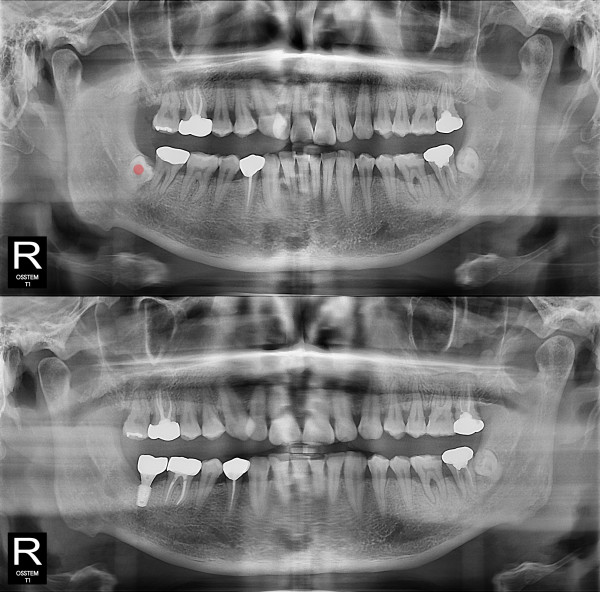

사랑니발치 완전 매복 사랑니

826e40416d712e6cd444a78bde93df4b_1767857522_0469.jpg